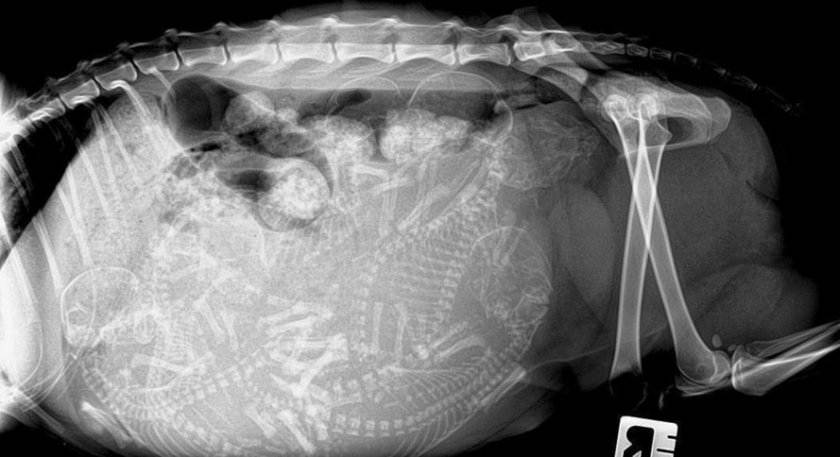

Рентген — метод это не самый полезный для самой кошки и будущих котят, поэтому прибегать к нему нежелательно. Увидеть четкие контуры плодов на рентгеновском снимке можно с 45-го дня беременности.

Ультразвуковое исследование — с его помощью можно не только увидеть будущее потомство, подсчитать количество малышей, но и услышать сердцебиение. Метод чаще всего применяется, если есть необходимость определить беременность кошки на ранних сроках.

Если раньше врач просто мог нащупать некоторое количество плодов в животе у животного, то с 40-го дня ветеринар скажет точное количество ожидаемых котят.